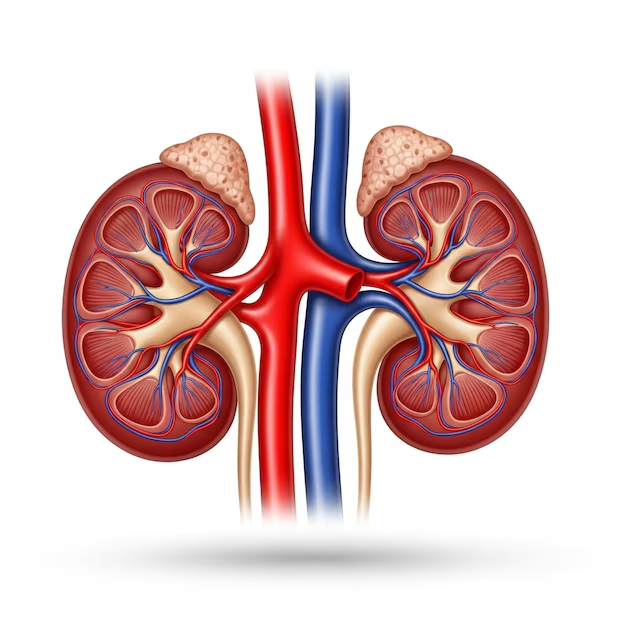

What is Laparoscopic Pyeloplasty and How Does It Work?

Laparoscopic pyeloplasty is a minimally invasive surgery that removes the blocked segment of the ureter and reconnects it to allow smooth urine flow.

During Laparoscopic Pyeloplasty in Raipur:

- Small keyhole incisions are made

- A laparoscopic camera provides clear visualization

- The narrowed or blocked segment is removed

- The ureter is reconstructed and reattached

Conditions Where Pyeloplasty is the Best Treatment Option

Laparoscopic Pyeloplasty in Raipur is recommended when the obstruction is significant and cannot be managed with medications alone.

- Congenital UPJ Obstruction

- Blockage Due to Scarring or Narrowing

- Recurrent Kidney Swelling

- Failed Previous Treatments

Technology and Techniques Used in Pyeloplasty

Advanced technology enhances the success of Laparoscopic Pyeloplasty in Raipur.

High-Definition Laparoscopic Visualization

A high-definition camera provides a clear, magnified view of the surgical area, allowing accurate identification and correction of the blockage.

Precision Suturing Techniques

Advanced suturing methods help in reconstructing the ureter effectively, ensuring proper urine flow and long-term success of the procedure.

Minimally Invasive Approach

Small keyhole incisions reduce tissue damage, resulting in less pain, minimal scarring, and a shorter hospital stay.